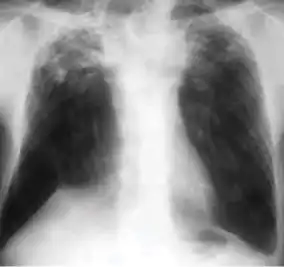

Dense homogenous opacity in right, middle and lower lobe of primary pulmonary TB.

Chest x-ray showing patchy opacification on the upper right and mid-zone lung with fibrotic shadows, as well as bilateral hilar lymphadenopathy.